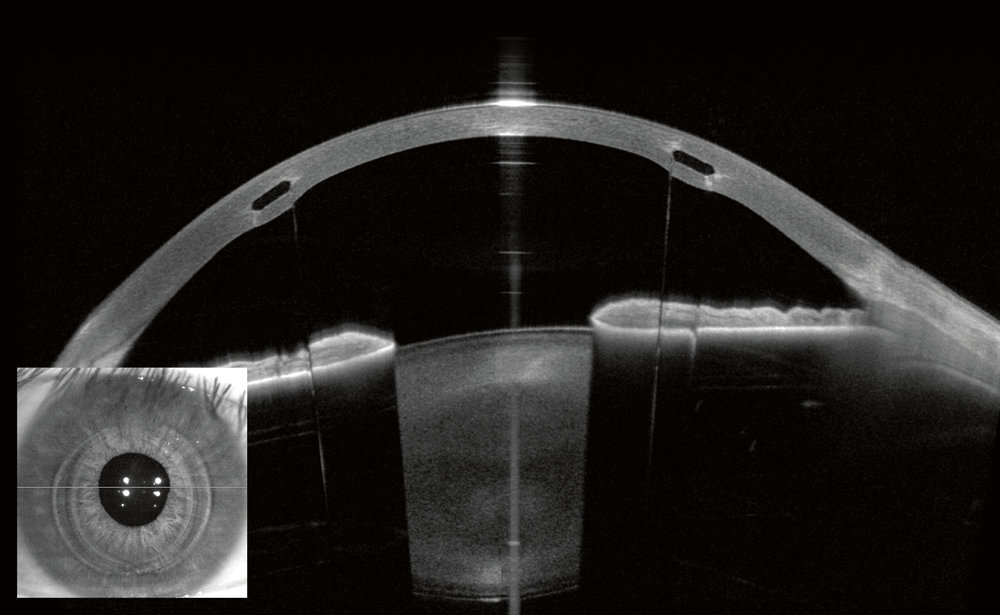

ANTERION® využívá kvalitu SWEPT Source OCT snímků s vysokým rozlišením k poskytování nejdůležitějších vyšetření a měření předního segmentu na jedné modulární, upgradovatelné platformě.

ANTERION® je založen na aplikaci Imaging App pro vizualizaci celého předního segmentu ve vysokém rozlišení a přizpůsobuje se různým klinickým potřebám se třemi volitelnými aplikacemi: Cornea App, Cataract App a Metrics App.

Aplikace ANTERION® Cataract App kombinuje klíčová měření pro plánování operace katarakty: analýzu rohovky, hloubku přední komory, tloušťku čočky a axiální délku. Optimalizovaná technologie SWEPT Source OCT umožňuje přesná měření a vizuální potvrzení pomocí snímků s vysokým rozlišením i přes výrazný šedý zákal.

Aplikace ANTERION® Metrics App nabízí výjimečně čisté snímky SWEPT Source OCT s přední komorou zobrazenou v radiálním zobrazení. OCT snímky s vysokým rozlišením poskytují základ pro přesné měření. Určete předdefinované parametry úhlu nebo proveďte měření dle libosti přizpůsobené klinickému případu.